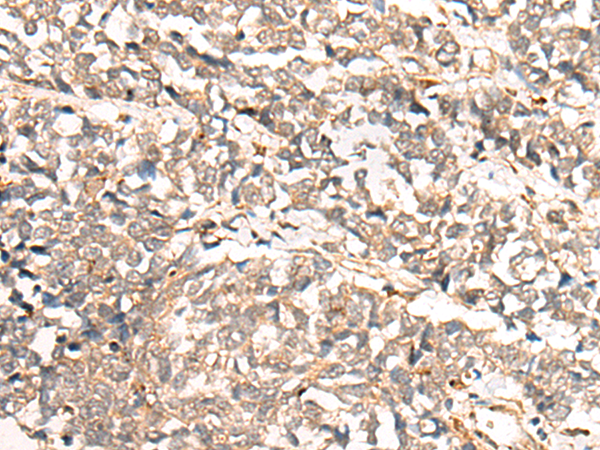

The image is immunohistochemistry of paraffin-embedded Human colorectal cancer tissue using 46969(COMMD1 Antibody) at dilution 1/35. (Original magnification: ?00)